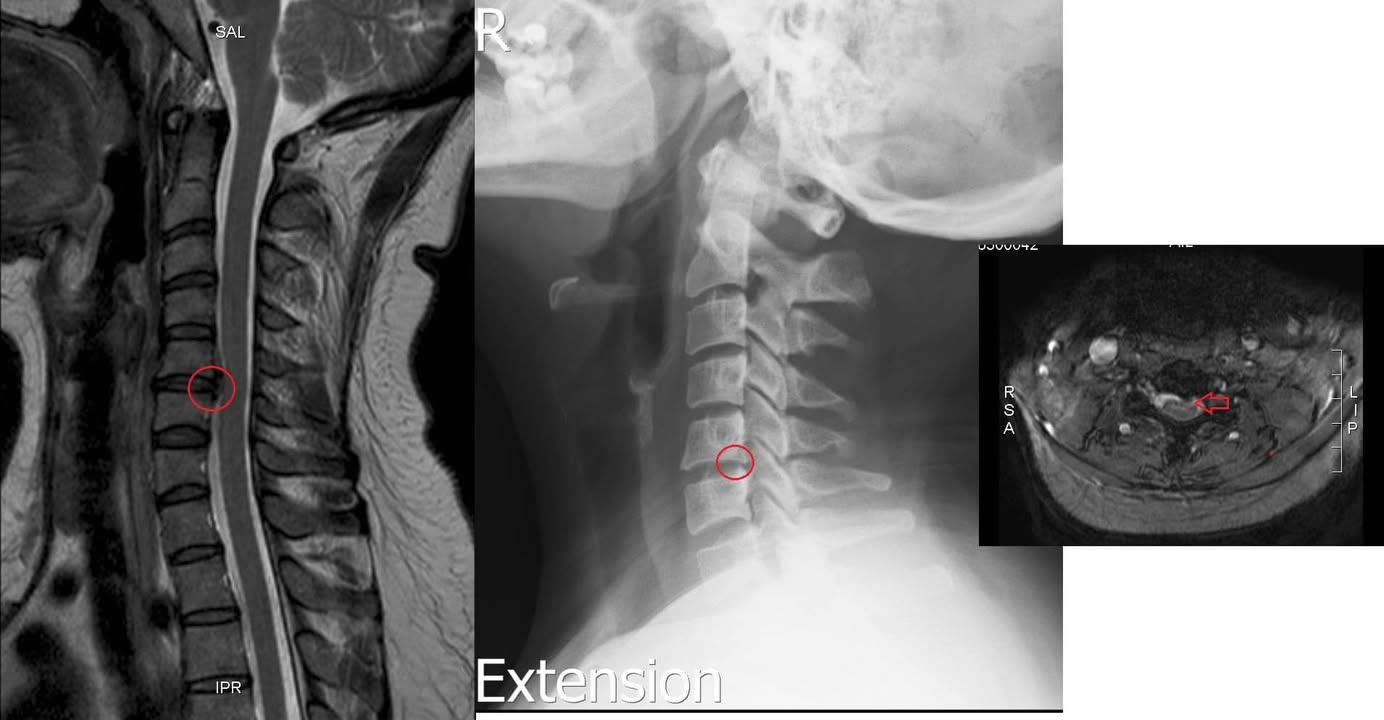

Cervical Spine Treatment Cases 頸椎治療案例 #疼痛三年頸椎病患者親手寫下治療紀錄 #交感神經型頸椎病 #症狀錯綜複雜 2020.10.02 #困擾四年多胸悶手麻頭暈醫案 #一切原因居然是頸椎出問題 #交感神經型頸椎病症狀錯綜... 2020.09.11 #交感神經型頸椎病引起的耳鳴 #耳鳴將近八個月終於得到重大改善 #曾經耳鳴到無法睡覺... 2020.08.22 #感謝板橋蘇先生熱情見證 #神經根型頸椎病卡壓 #曾痛痛到左手無法騎單車撥桿 #麻脹刺... 2020.08.04 #後縱韌帶鈣化引起椎管狹窄 #痛到完全無法睡覺長達半年以上 #原本已經準備開刀最後逆... 2020.07.16 #牽一頸而動全身的特殊醫案 #兩分鐘瞭解交感神經型頸椎病 #絕望的黑暗人生看到一絲希... 2020.07.03 #長達七年的頸椎疼痛是怎麼回事 #神經根型頸椎病 #低頭族跟家庭主婦辛苦了 #逆轉勝醫... 2020.07.01 #頸椎整合中醫微創療法 #感謝新竹黃大哥熱情見證 #逆轉勝成真醫案 2020.06.25 #頸椎病手術後也要要好好保健 #毛巾操很重要再度上場 #感謝某大醫學中心主任見證 2020.06.24 #這些症狀很可能都是頸椎出問題 #患者看七種不同科別醫師找不出原因 #交感神經型頸椎... 2020.06.09 #消失的頸椎曲線能夠回來嗎? #核磁共振前後對比椎管容積打開 #脊椎整合中醫微創療法❤... 2020.06.05 #感謝新竹薛大哥熱情見證 #頸椎整合中醫微創療法 治療:4/21~5/30(八次) 效果顯著... 2020.05.30 從宜蘭來的游小姐患者熱情見證 頸椎整合中醫微創療法 逆。轉。成。真。 2020.05.29 #脊髓型頸椎病案例 2020.05.26 #感謝新北市黃小姐熱情見證 #疼痛時間超過一年 #晨起麻痛到不行的日子長達半年以上 #... 2020.05.16 ← 上一頁 5 6 7 8 9 下一頁 →